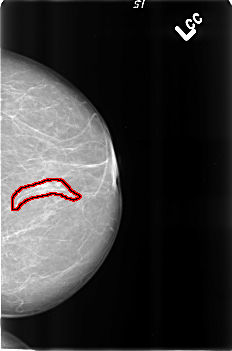

FILE: B_3190_1.LEFT_CC.OVERLAY

TOTAL_ABNORMALITIES 1

ABNORMALITY 1

LESION_TYPE CALCIFICATION TYPE VASCULAR DISTRIBUTION N/A

ASSESSMENT 2

SUBTLETY 4

PATHOLOGY BENIGN_WITHOUT_CALLBACK

TOTAL_OUTLINES 1

BOUNDARY